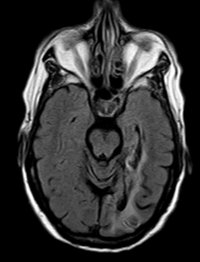

Posteriorinfarkt

Posteriorinfarkt T1 mit KM - axial

Posteriorinfarkt Flair Sensitiv - axial